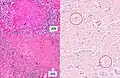

Tuberculosis of the lungs

A case of miliary tuberculosis in an 82-year-old woman: